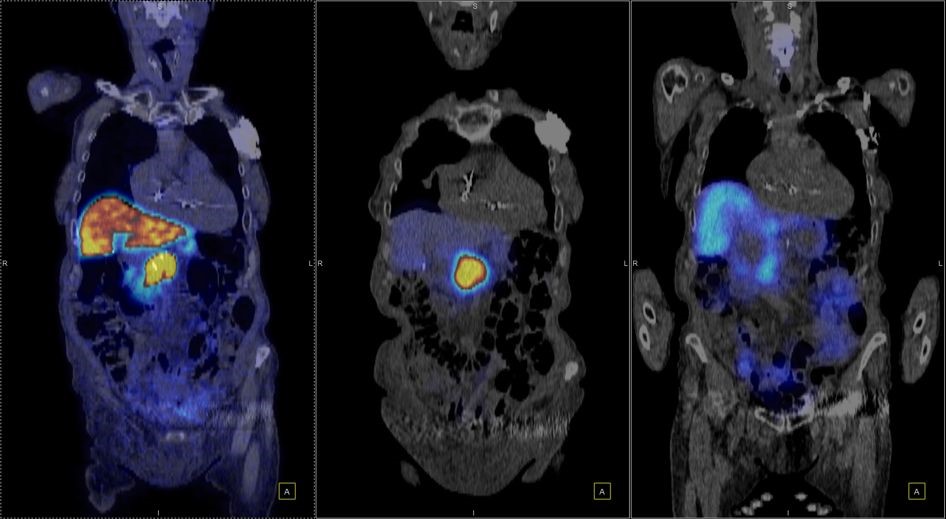

Η Τομογραφία Εκπομπής Ποζιτρονίων (PET) αποτελεί μια εξειδικευμένη μέθοδο της Πυρηνικής Ιατρικής που χρησιμοποιεί μοριακή απεικόνιση για να εντοπίσει και να παρακολουθήσει φυσιολογικές και παθολογικές λειτουργίες του οργανισμού. Συνδυάζοντας τη λειτουργική απεικόνιση της PET με την ανατομική πληροφορία της αξονικής τομογραφίας (CT), η υβριδική εξέταση PET/CT παρέχει εικόνες υψηλής ευκρίνειας και τη δυνατότητα ποσοτικής αξιολόγησης των βιολογικών μηχανισμών σε κυτταρικό επίπεδο.

Η PET/CT αποτελεί εξαιρετικά προηγμένη τεχνική της σύγχρονης ιατρικής απεικόνισης και χρησιμοποιείται τόσο για τη διάγνωση όσο και για την παρακολούθηση της ανταπόκρισης στη θεραπεία.

Στην ογκολογία, η PET/CT συμβάλλει με εξαιρετική ακρίβεια:

Η εξέταση είναι ανώδυνη και ασφαλής, πραγματοποιείται μετά από ενδοφλέβια χορήγηση ραδιοφαρμάκου (συνήθως ¹⁸F-FDG) και καλύπτει συνήθως ολόκληρο το σώμα – από την κορυφή της κεφαλής έως τα πέλματα.

Συνδυάζουμε στοχευμένα ραδιοφάρμακα που απεικονίζουν και θεραπεύουν τον ίδιο μοριακό στόχο. Στο ΥΓΕΙΑ το πρόγραμμα αφορά:

Ο στόχος είναι σαφής: να δώσουμε τη σωστή δόση, στο σωστό σημείο, τη σωστή στιγμή.